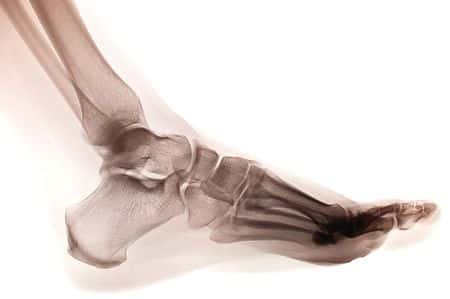

This case involves a fifty-two-year-old male patient with a past medical history of obesity, hypertension and hyperlipidemia. The patient slipped on ice and fell on his way to work. The fall resulted in a fracture of the patient’s right ankle. He was treated in the emergency room and referred to a podiatrist DPM physician surgeon for surgical repair of the fracture. The surgery went well with no complications intraoperatively. The patient was discharged to rehab. Approximately six weeks after the operation, the patient presented to the treating podiatrist DPM physician’s office for a follow up visit. During the consultation the patient complained of a three day history of shortness of breath. The treating physician performed three checks of the patient’s heart rate. On each occasion the patient was found to be very tachycardic. Further examination by the physician revealed swelling of the patient’s right leg. This was documented in the patient’s medical notes as well. The treating podiatrist DPM physician advised the patient to see his family doctor about the tachycardia, shortness of breath and lower extremity swelling. The physician did not convey any sense of urgency to the patient nor did he explain that these symptoms could be indicative of a life threatening condition. Instead, he advised the patient that he needed to consult his family doctor before he could be cleared for anesthesia for a second surgery to remove surgical pins from the treated ankle which was due to take place in the next few weeks. The physician made no emergency referral and took no other actions to address the patient’s symptoms. Two days after the consultation with the treating physician the patient was found dead in his home by a relative. An autopsy revealed the cause of death to be a massive pulmonary embolism.